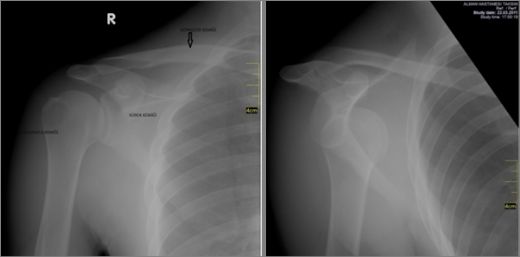

Teşhis Yöntemleri Kürek kemiği kırığı teşhisi genellikle fiziksel muayene ve görüntüleme yöntemleri ile yapılmaktadır.